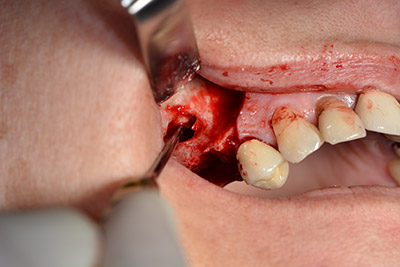

The implant was then placed and the bone built up. In this case, because of the size of the augmentation region, autologous bone chips, harvested with an osseous trap as drilling chips from implantation 16 and fenestration 14, were mixed with bone replacement material.

An absorbable membrane was used as the barrier in the buccal direction and covered the augmentation. Finally, saliva-proof sutures were placed (Fig. 15 to 19).

Augmentation with autologous bone

Image 15

Image 16